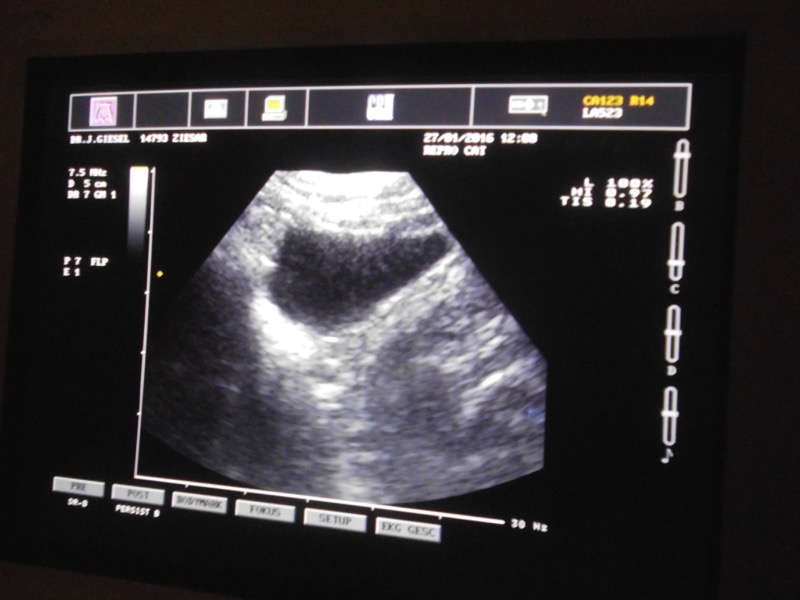

Da die Tiere nicht durch Schmerzäußerungen auffallen und oft auch kein Blut im Urin feststellbar ist, müssen sie sorgfältig in ihrem Verhalten beobachtet werden (u.a. Rutschen auf dem Bauch, abgeschubbertes Fell, Lecken, veränderter Gang, Verweigerung beim Springen, usw.)

Unsere Tierpfleger beobachten natürlich auch immer genau; aber wir gehen bei uns gern auf "Nummer Sicher", denn wir möchten nicht, dass irgendein Leiden unentdeckt bleibt. So waren dieser Tage unsere Meerschweinchen und Kaninchen zur Vorsorgeuntersuchung bei unserer Tierärztin angemeldet.

Eine Untersuchung mit Ultraschall ist ohne Narkose möglich und völlig schmerzfrei. Etwas stressig ist die Prozedur natürlich trotzdem für die Tiere - aber es ging alles sehr zügig und ist immer noch besser, als sich unerkannt krank im Gehege zu quälen. Viele Menschen wissen aus eigener Erfahrung um die schlimmen Schmerzen von Harnsteinen. Deshalb kann man auch privaten Tierhaltern nur empfehlen, ab und zu einen Tierarzt prüfen zu lassen.

Unsere Tiere waren alle ohne Befund. Ein Meerschweinchen musste zur genauen Abklärung noch geröntgt werden. So sind wir nun erst einmal wieder beruhigt.